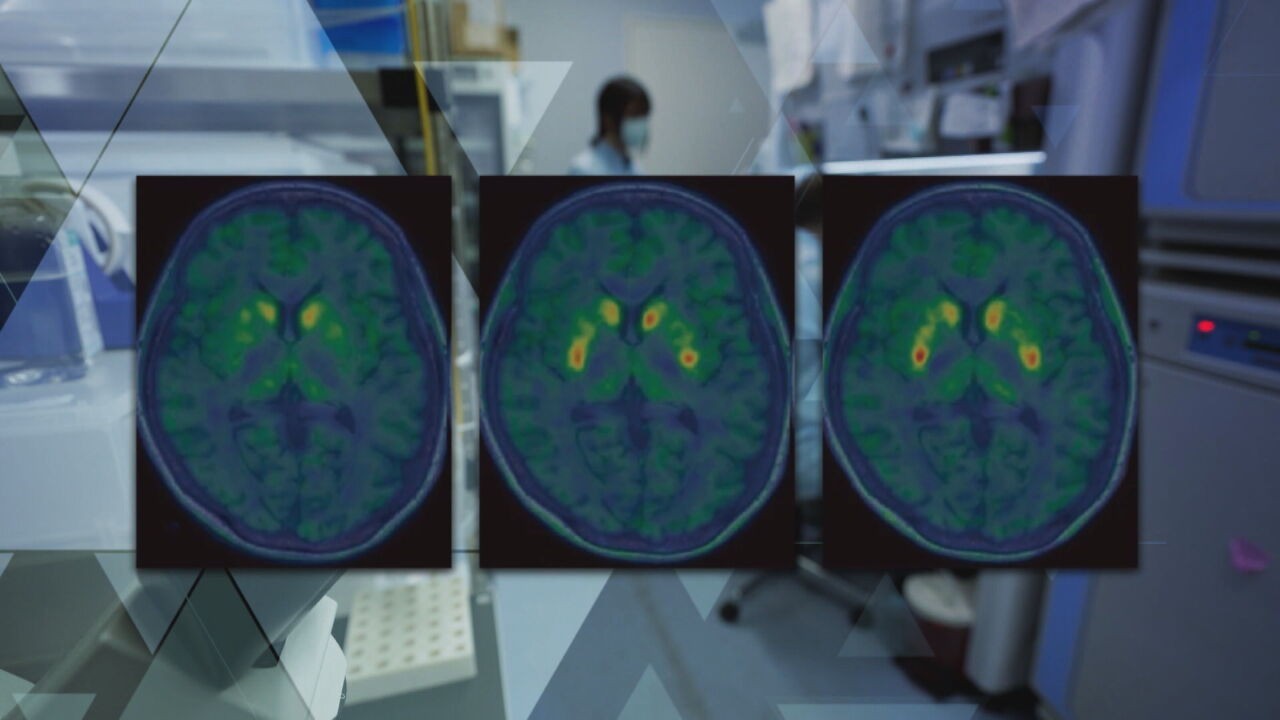

Como funciona a terapia celular que tenta restaurar a dopamina no cérebro de pacientes com Parkinson

A terapia ainda é experimental e, até agora, foi aplicada em pacientes com mais de cinco anos de diagnóstico, que apresentam flutuações motoras e não respondem bem ao tratamento convencional com levodopa — principal medicamento usado hoje, mas que pode causar efeitos colaterais ao longo do tempo.